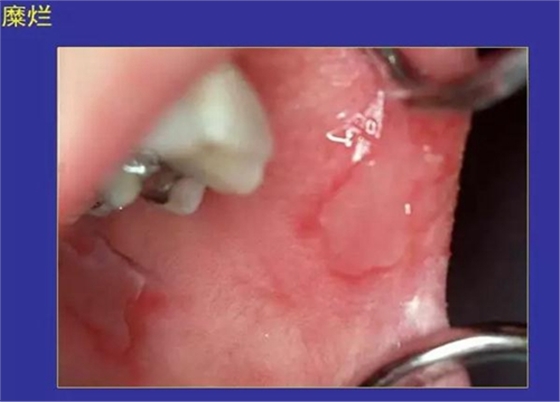

5.糜爛:黏膜表淺缺損,不損及基底細胞層。

正??谇火つぜ俺R姴p圖